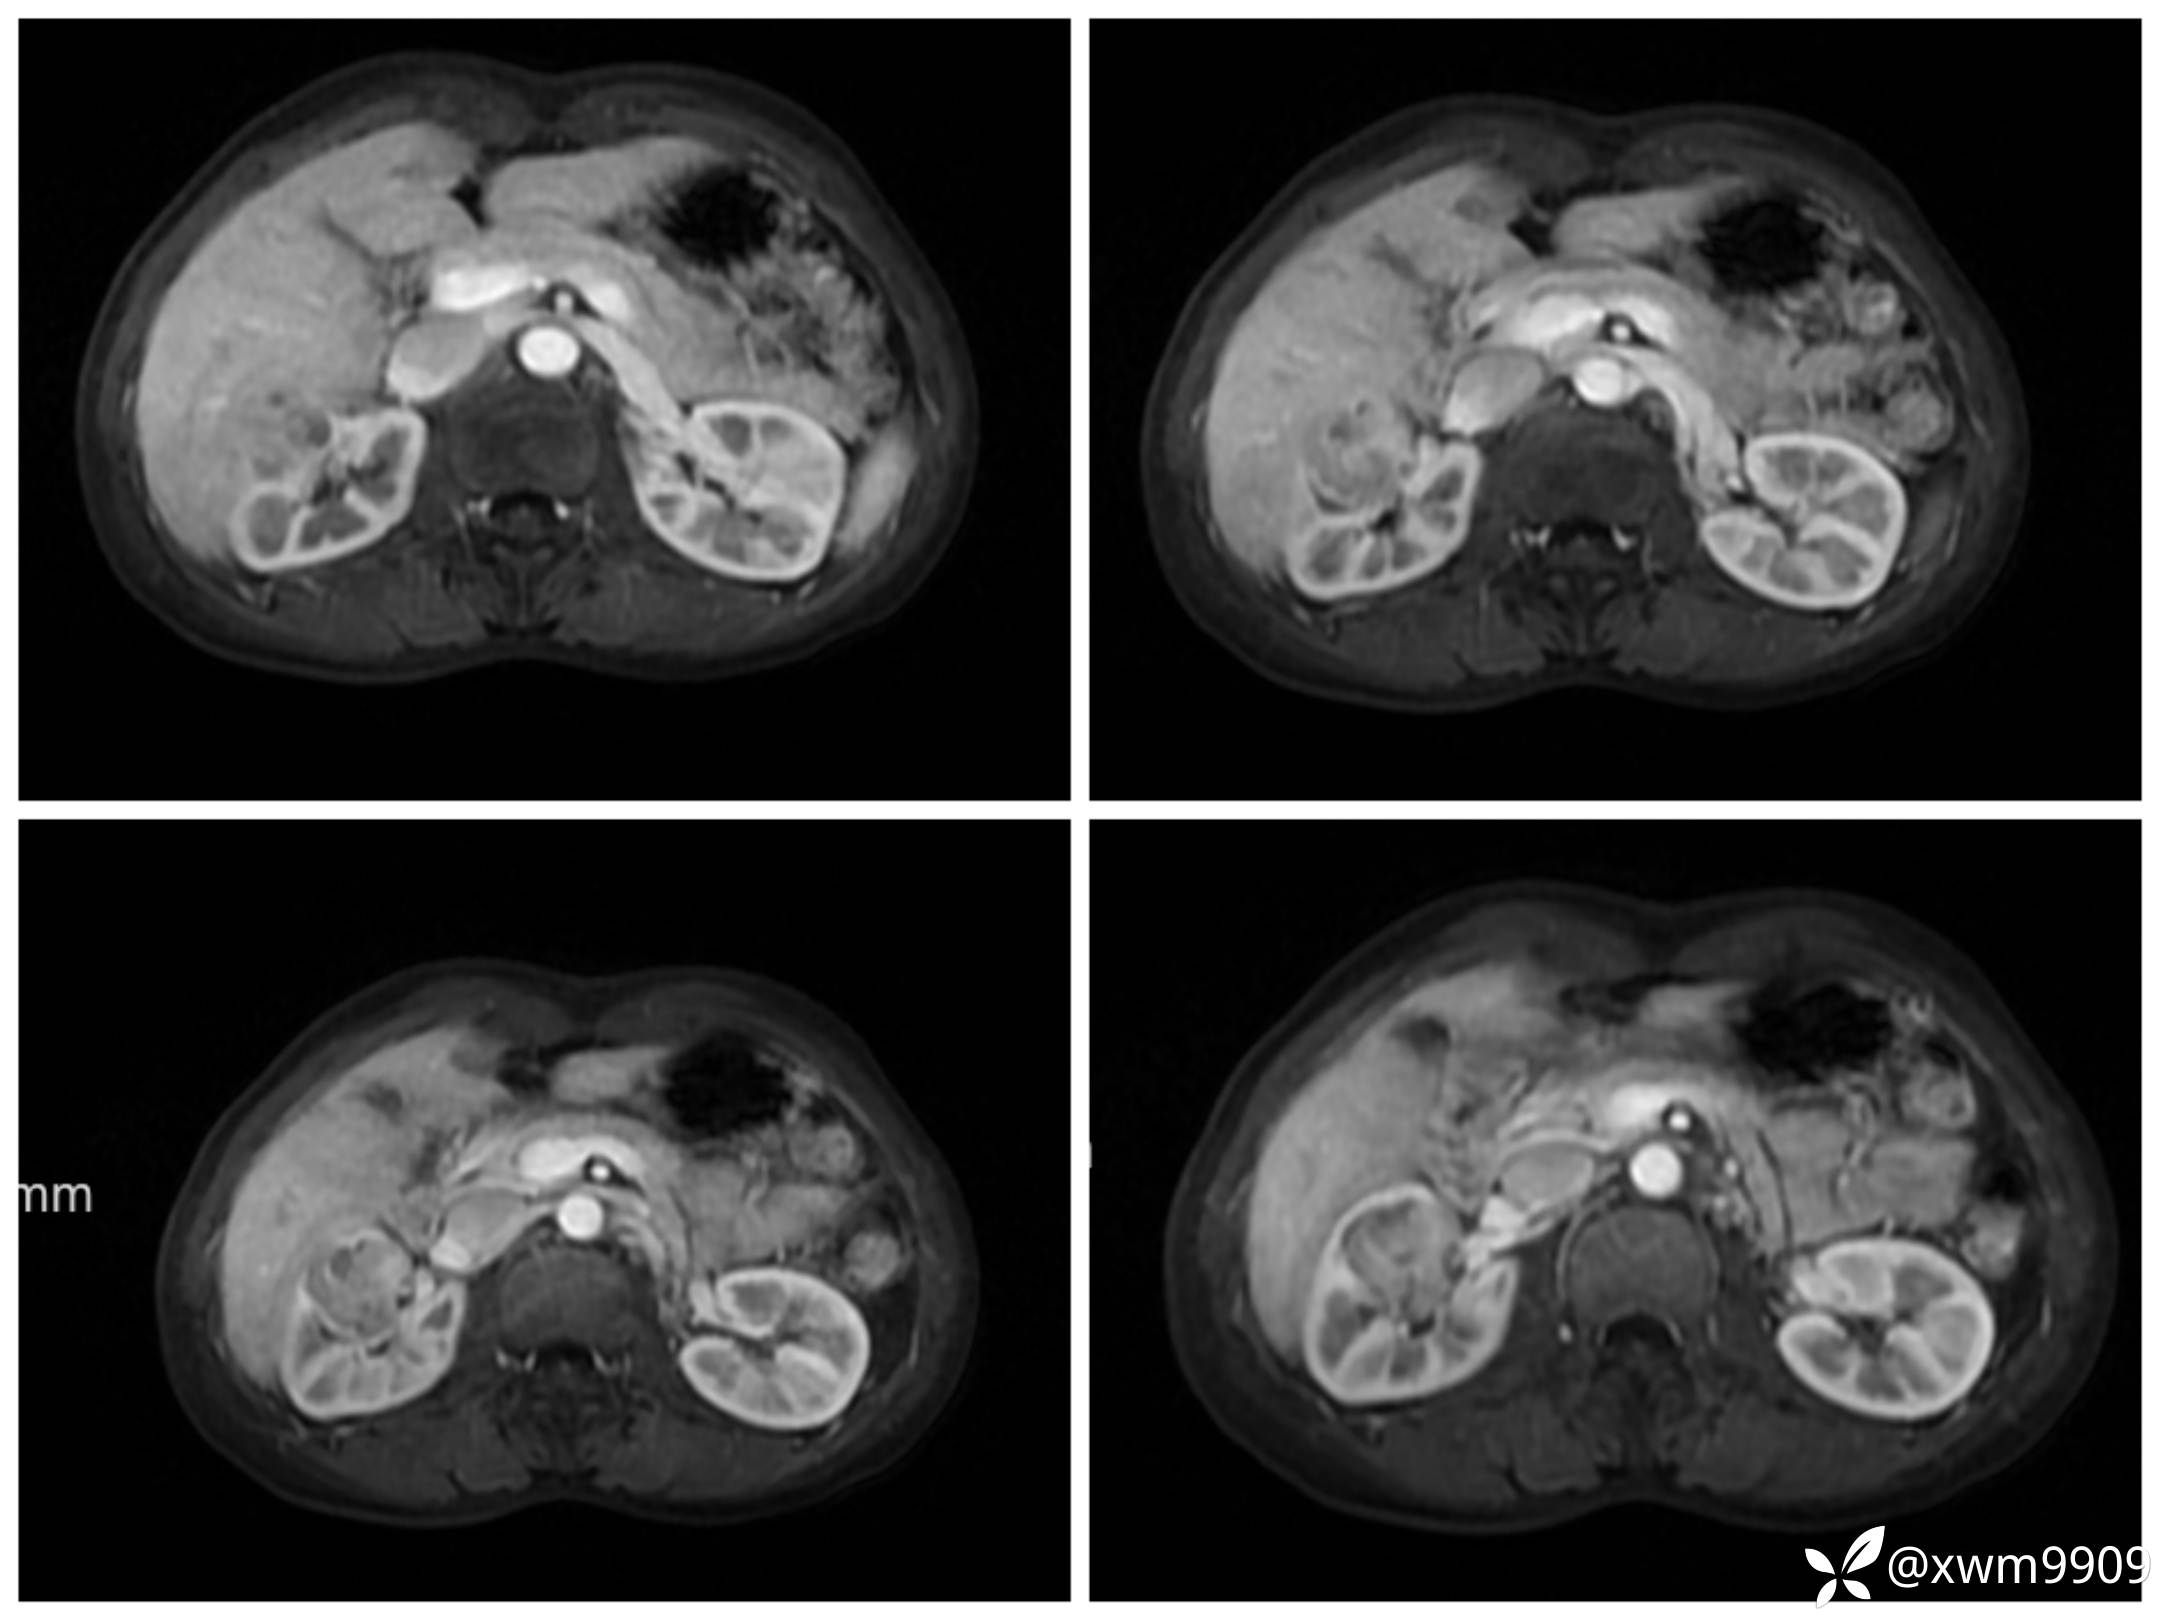

LAvA:

A:

v:

平衡期: